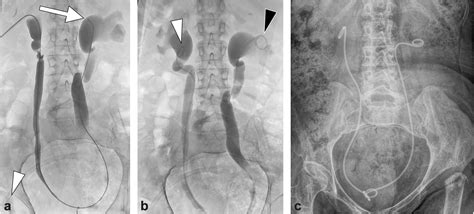

A bladder stent, commonly referred to by medical professionals as a ureteral stent, is a thin, flexible tube made of medical-grade plastic or silicone. It is placed within the ureter—the duct that carries urine from the kidney to the bladder—to ensure that urine flows freely, especially after surgery or if the ureter is narrowed due to a stone or other obstruction.

The stent acts as a temporary internal drainage system, allowing the ureter to heal without the risk of blockage. While effective, these stents are generally designed for short-term use and must be removed once the underlying condition has resolved. Leaving a stent in for too long can lead to complications such as infection, encrustation (mineral buildup), or discomfort.